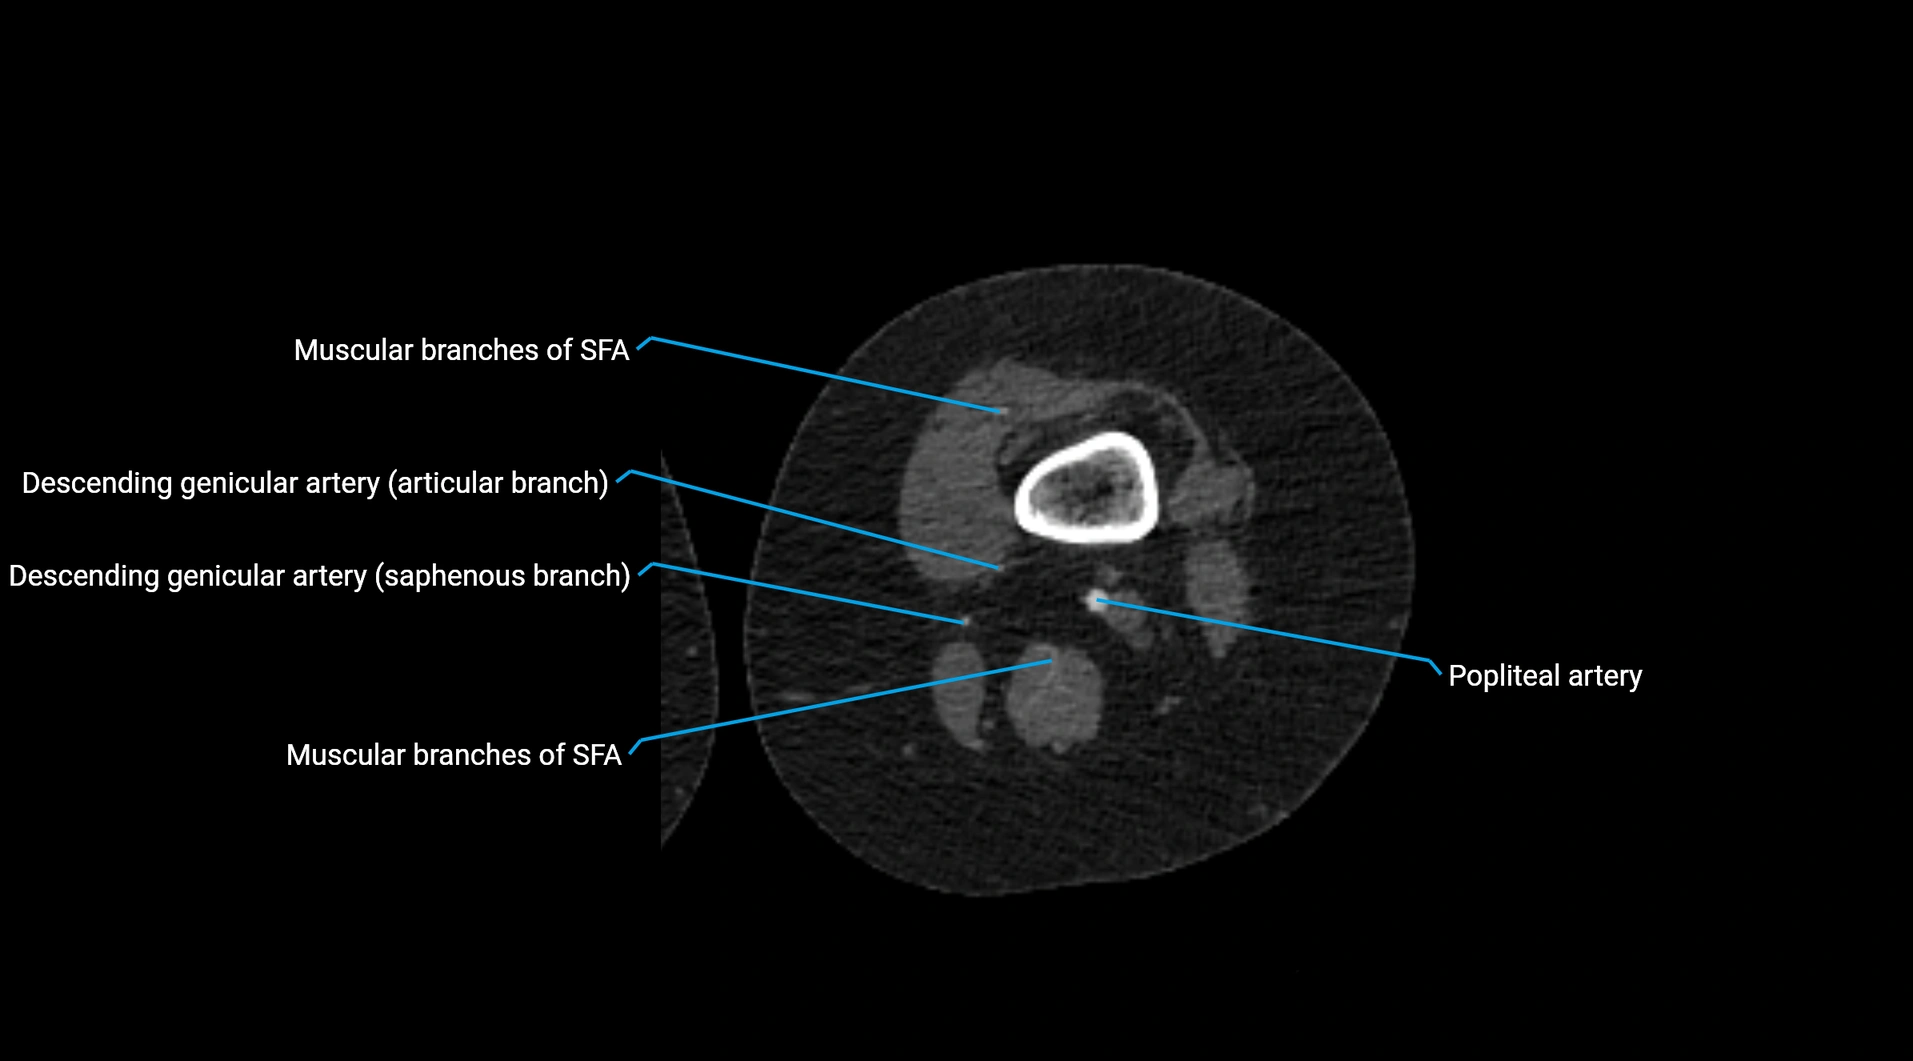

CT images

image